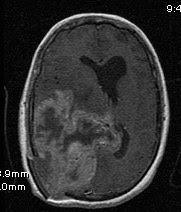

Glioblastoma multiforme GBM – radiology Treatment of gliomata Observation – low grade Surgery Treatment of gliomata Radiotherapy 60Gy in 30# over 6 weeks +/- Temozolamide chemotherapy (25% alive at 2 years) Or 30Gy in 6# over 2 weeks ... Fetch Doc